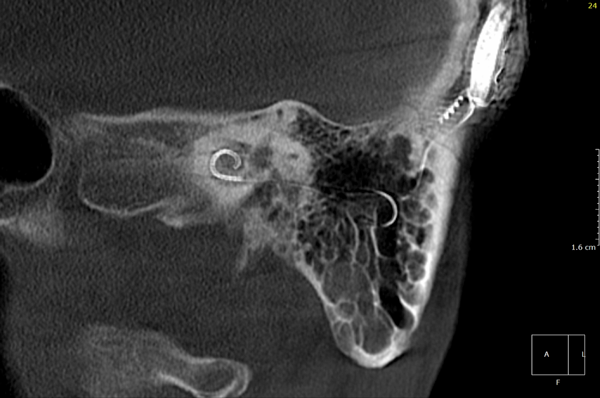

Both patients were imaged immediately with CBCT using SCANORA® 3Dx (Soredex, Tuusula, Finland). The field of view (FOV) was 140 x 165 mm and voxel size 0.2 mm. Imaging parameters were 90 kV, 8 mA, 4.00s. Standard 1 mm axial, coronal and sagittal reformations were made, as well as MIP and 3D reconstructions using OnDemand3D™ software (Cybermed, Seoul, South Korea).

CBCT proved to be optimal for imaging of these implants because of the superior bony delineation and nearly artefact free images. All four parts, i.e. the receiver stimulation part, extracochlear electrode implanted on the surface of the temporal bone, the extracochlear electrode plate and the intracochlear electrode array could be well imaged with CBCT.

On CBCT all four of the important parts of the implant were very well seen both on the axial slices and three dimensional surface reconstruction images. The implant is placed on magnetic plates, and the extracochlear part was seen in an abnormal separated position. The intracochlear electrode array showed no signs of separation in either of the cases. The intracochlear electrodes were well seen in both of the cases.

The optimal images of these two patients are shown in the radiographic illustrations in Figures 1-7.

Figure 1: Patient 1 - Sagittal oblique reformatted CBCT image showing the intracochlear portion of the implant.